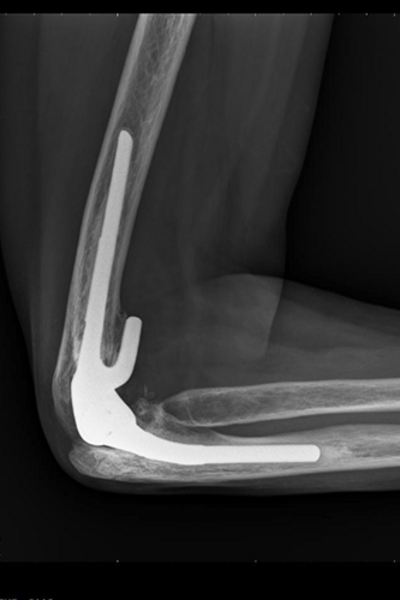

Nachher

Ellbogenröntgen ap

Ellbogengelenksendoprothese

2 Jahre nach der Operation